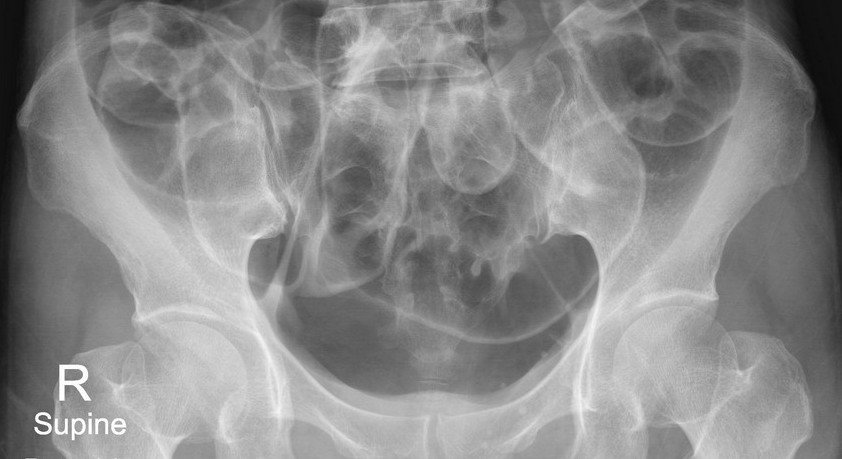

History :  A 60-year-old man. The patient had colonography and polypectomy with abdominal pain

D. All answers correct:

Large and small bowel dilatation due to post colonography

- Free air due to

rupture of the colon

Abdominal Radiograph :

* Free air can be detected on an abdominal radiograph

* Important signs on supine film include:

Plain abdominal radiograph :

Double wall sign

Lucent liver sign

Lateral umbilical ligament sign (inverted "V" sign)